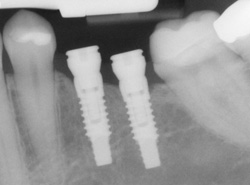

An implant is a synthetic tooth root in the shape of a post that is surgically placed into the jawbone. The “root” is usually made of titanium (the same material used in many replacement hips and knees), a metal that is well suited to pairing with human bone. A replacement tooth is then fixed to the post. The tooth can be either permanently attached or removable. Permanent teeth are more stable and feel more like natural teeth.

Single or Multiple Implants

Implants are versatile. If you are only missing one tooth, one implant plus one replacement tooth will do the trick. If you are missing several teeth in a row, a few strategically placed implants can support a permanent bridge (a set of replacement teeth). Similarly, if you have lost all of your teeth, a full bridge or full denture can be permanently fixed in your mouth with a strategic number of implants.